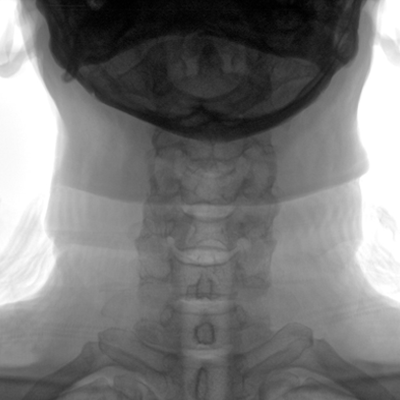

臨床適用科室:骨科、普通外科、矯形外科、創(chuàng)傷外科、泌尿外科、脊柱外科、疼痛外科、消化科、婦科等科室。

大尺寸動態(tài)平板探測器,高DQE、低噪聲、圖像清晰。采用多分辨率圖像增強處理技術(shù),不同部位不同圖像處理算法,滿足客戶多樣化的需求。

多角度自由旋轉(zhuǎn),滿足患者復(fù)雜擺位需求。